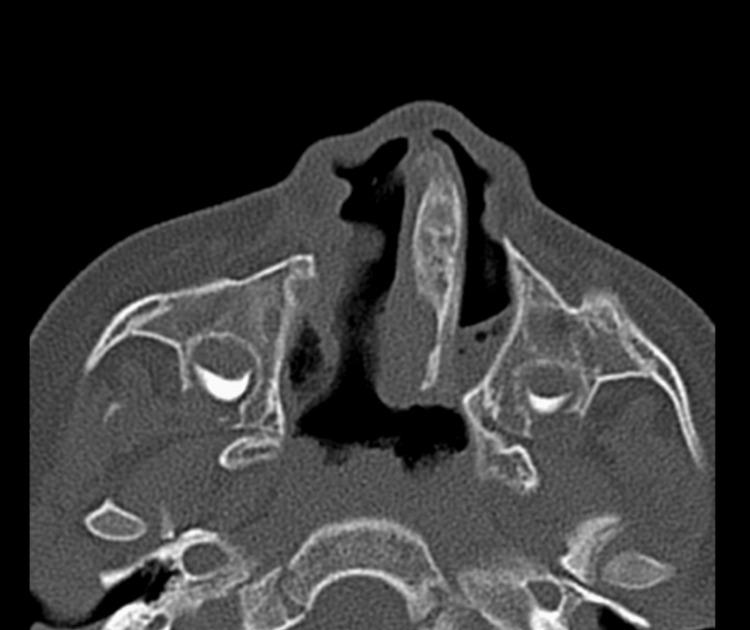

Introduction Choanal atresia (CA) is an uncommon congenital anomaly. There are various syndromes that are associated with CA. The purpose of this study is to determine the differences in CA's presentation and outcome when associated with other congenital anomalies and syndromes. Method This is a retrospective review study of all children (18 years and younger) who underwent CA repair in a tertiary referral healthcare center from January 2005 to April 2022. Demographics, comorbidities, radiological testing, operative reports, and outpatient reports were collected. Success was determined as a child with bilateral patent choana that is able to breathe from both nostrils comfortably. Result Twenty-four patients met the criteria for inclusion in this study. Bilateral CA was present in 15 (62.5%) patients. Mixed CA was the most common variant. There were various congenital anomalies in association with CA patients who are yet to be classified into a syndrome. The most common congenital anomaly was cleft lip and palate. Bony and mixed types were significantly associated with non-syndromic patients (p<0.05). Twenty patients (83%) were diagnosed with CA at age of less than one year, and four patients were diagnosed after one year of age. There were 36 surgeries performed on 24 patients, of which 27 were endoscopic and nine were using Hugher dilator. The overall success rate for CA repair was 50%. The median number of revisions per patient was 0.5. Conclusion CA is a challenging anomaly to repair. There are various factors that influence the outcome of children with CA. Otolaryngologists should counsel the patient and their families regarding possible need for revision especially in those with other craniofacial anomalies.